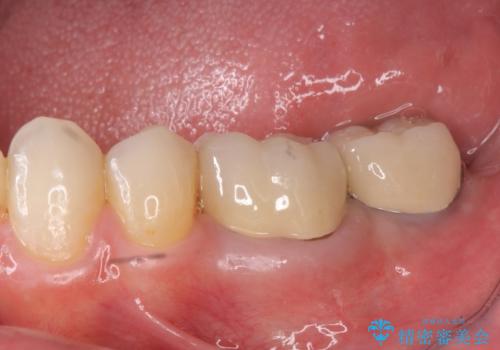

[フルジルコニアクラウン] 老朽化した銀歯を白く